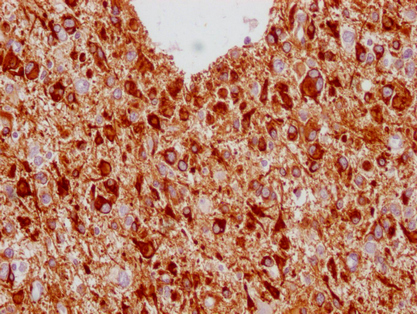

IHC image of CSB-MA293354 diluted at 1:100 and staining in paraffin-embedded human glioma cancer performed on a Leica BondTM system. After dewaxing and hydration, antigen retrieval was mediated by high pressure in a citrate buffer (pH 6.0). Section was blocked with 10% normal goat serum 30min at RT. Then primary antibody (1% BSA) was incubated at 4°C overnight. The primary is detected by a Goat anti-mouse IgG polymer labeled by HRP and visualized using 0.05% DAB.